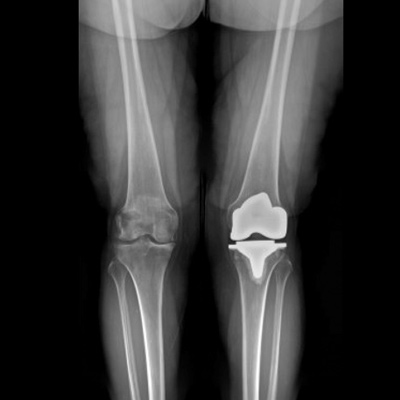

Anterior-Posterior View Total Knee Replacement

R knee: Mechanical Alignment

L knee: Kinematic Alignment